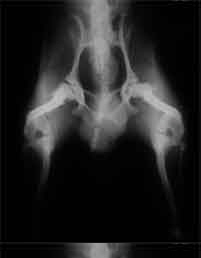

HD-und-Coxarthrose-extrem

Extremform einer dysplastischen Hfte mit Luxation der Oberschenkelkpfe und beidseitiger schwerer Arthrose